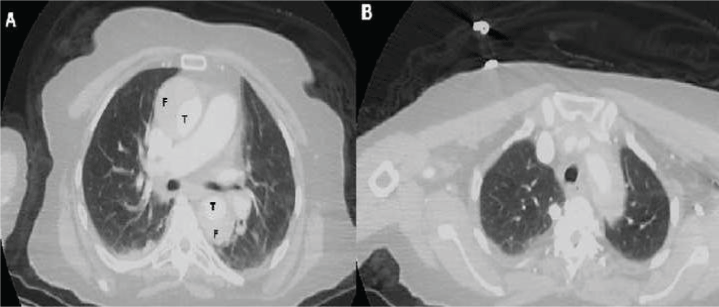

This concerns the case of an 82-years-old man who had previously been diagnosed with acute Stanford Type A aortic dissection and who refused surgical intervention. The third year following the diagnosis of aortic dissection, the patient was hospitalized because of chest pain, shortness of breath, fatigue and dizziness. A grade 4/6 diastolic murmur was heard on auscultation. Chest x-rays showed a right pleural effusion. Computed tomography demonstrated a Stanford Type A aortic dissection and dilatation of the ascending aorta (Figure 1). There was an intimal flap, enlarged patent false lumen and true lumen with mural thrombus in the ascending aorta. The lesion was approximately 10 cm in diameter - the largest ever reported - and resulted from chronic aortic dissection.

Figure 1: A) Computed sequential tomographic images of an 82-year-old man who diagnosed a chronic Stanford Type A aortic dissection. CT-scan illustrated dissection of the ascending aorta, dilatation of the ascending aorta and circulation in both the true (T) and the false (F) lumens. T denotes the true lumen and F denotes the false lumen; B) Contrast-enhanced tomography image showing aortic arch and branches in Stanford Type A dissection patient. View Figure 1